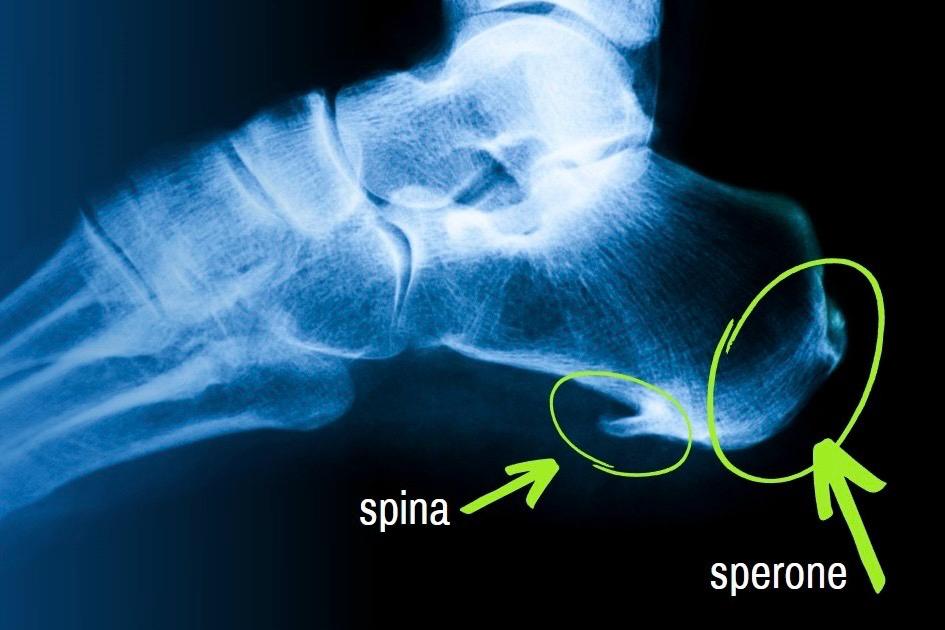

La spina è un piccolo sperone osseo che si forma come risposta a uno stress meccanico cronico. Quando il piede è costretto a lavorare in una condizione di carico scorretto o di trazione anomala della fascia plantare, il periostio reagisce depositando calcio nella zona d’inserzione del tendine.

Il corpo, in pratica, “costruisce” la spina per difendersi.